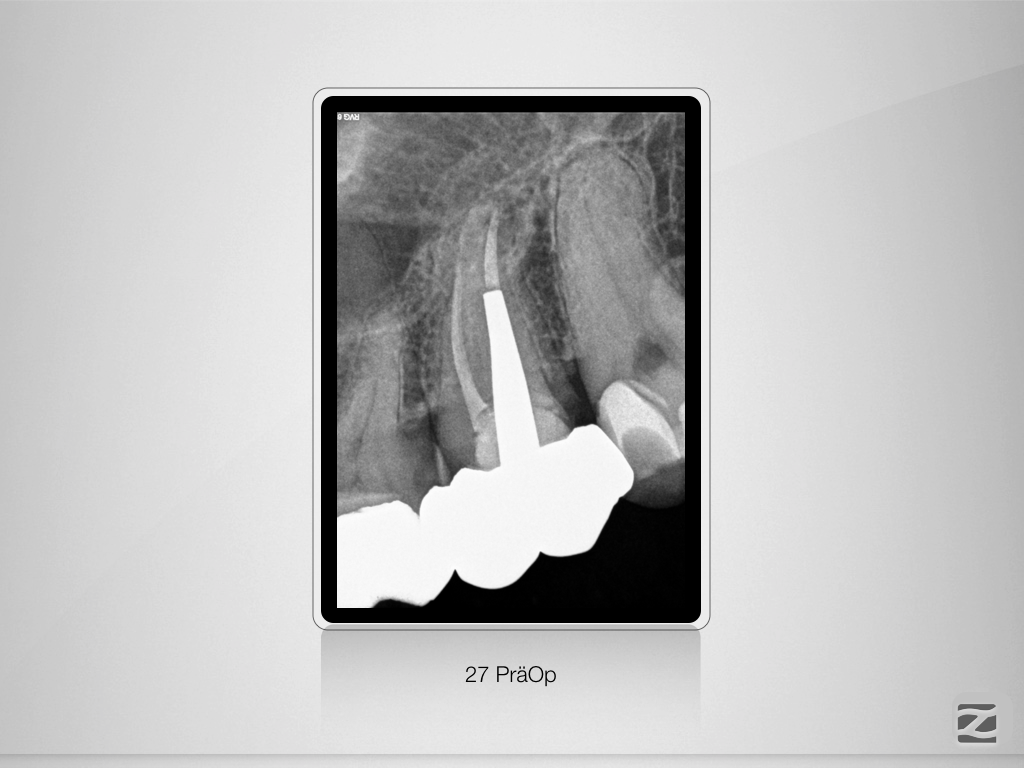

27D.001

Der weiße Tod